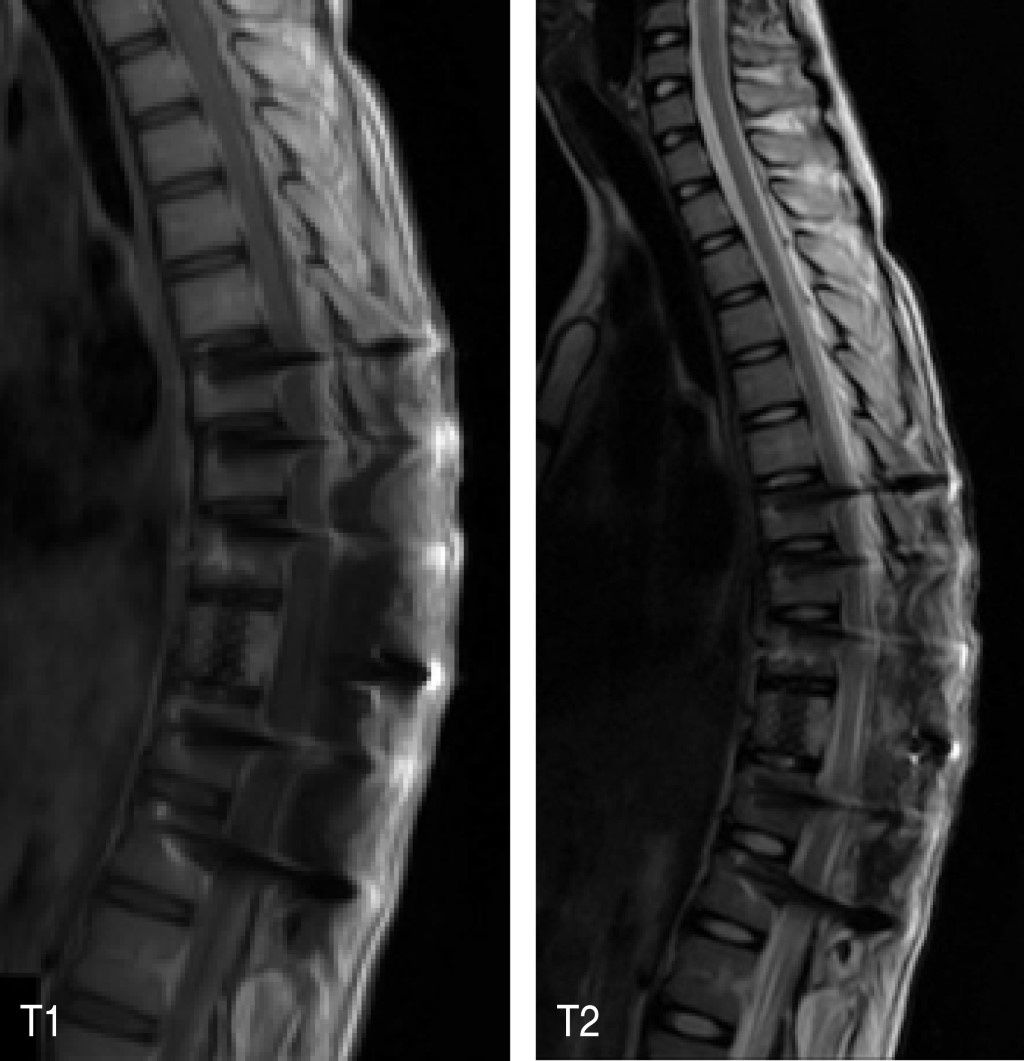

Figure 3